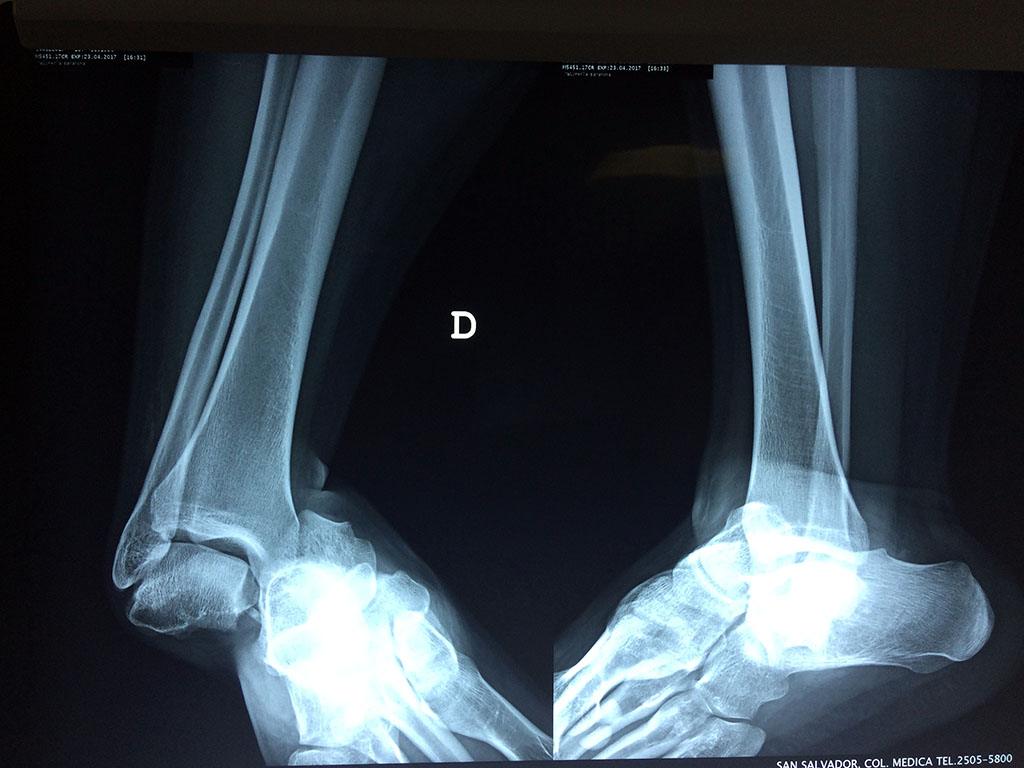

Una fractura de tobillo es la rotura de uno o más de los huesos del tobillo. Estas fracturas pueden ser:

- Parciales (el hueso está sólo parcialmente fisurado, no del todo).

- Completas (el hueso está perforado y está en 2 partes).

- Producirse en uno o ambos lados del tobillo.

Algunas fracturas de tobillo pueden requerir cirugía si:

- Los extremos de los huesos están desalineados entre sí (desplazados).

- La fractura se extiende hasta la articulación del tobillo (fractura intra-articular).

- Los tendones o ligamentos (tejidos que sujetan los músculos y los huesos entre sí) están rotos.

- El médico cree que sus huesos probablemente no sanen apropiadamente sin cirugía.

- El médico considera que la cirugía puede permitirle una recuperación más rápida y confiable.

- En los niños, la fractura involucra la parte del hueso del tobillo donde el hueso está creciendo.